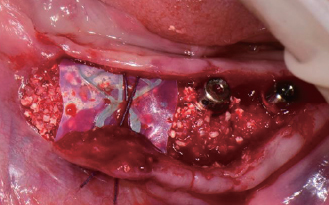

Wifi-Mesh 준비

Wifi-Mesh 형태 형성 *

Wifi-Mesh 장착

#33, 34, 35 & 36

Implant 식립

절개(Releasing incision)

골 이식

Wifi-Mesh 위치시킴

Membrane holding suture

봉합